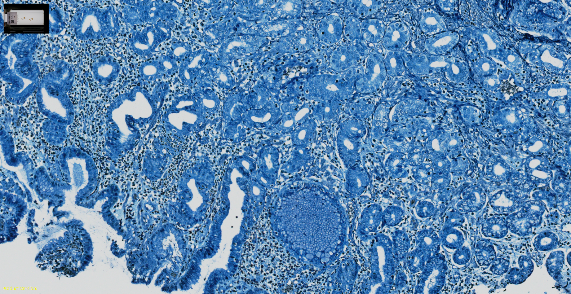

清晰捕捉细胞学样品的图像

SLIDEVIEW VS-M1

其他领军品牌

清晰捕捉各种组织和染色的细节

胃组织,H&E(苏木素和伊红)染色

胎盘波形蛋白(Vimentin)的免疫组化染色(IHC)

人类结肠组织,Warthin-Starry(WS)染色

胃组织,Giemsa染色